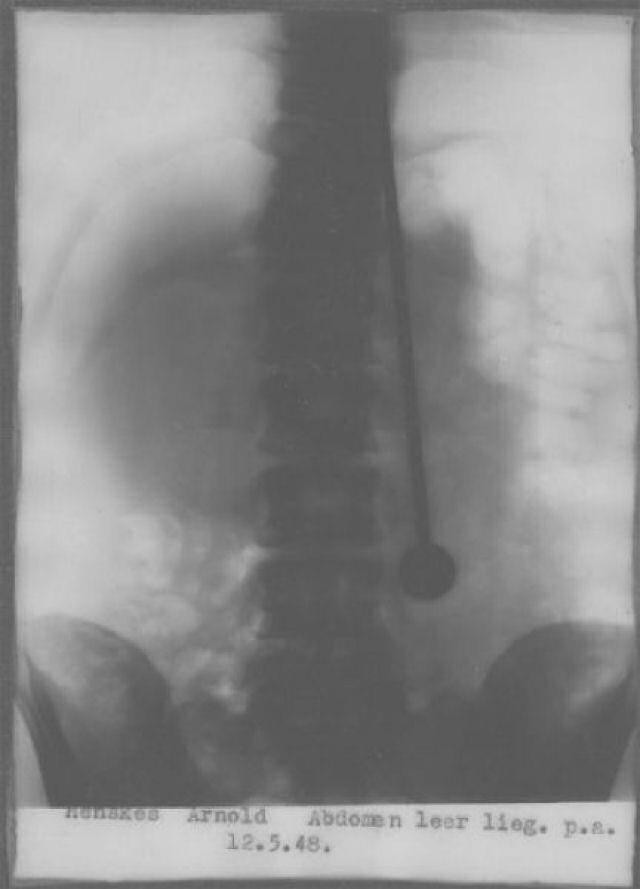

Vào tháng 5 năm 1948, Mirin Dajo nghe theo "tiếng gọi trong đầu" và nuốt một cây kim rất lớn xuống dạ dày. Đúng 2 ngày sau, ông rơi vào trạng thái nguy hiểm và phải làm phẫu thuật để loại bỏ chiếc kim đó. Không may, Mirin không qua khỏi và trút hơi thở cuối cùng vào ngày 26/5/1948, hưởng dương 36 tuổi.

Mirin Dajo đã trình diễn đâm kiếm xuyên qua người tới 500 lần. Có vẻ như chính thứ giúp ông nổi tiếng đã cướp đi sinh mạng của ông. Khám nghiệm tử thi Dajo, bác sĩ cho rằng nguyên nhân chính của cái chết là do vỡ động mạch chủ. Tuy nhiên, nhiều người đi theo Mirin đã chối bỏ điều này.

Ảnh chụp X-quang vào ngày 12 tháng 5 năm 1948 cho thấy một cây kim đang nằm gọn trong bụng Dajo.